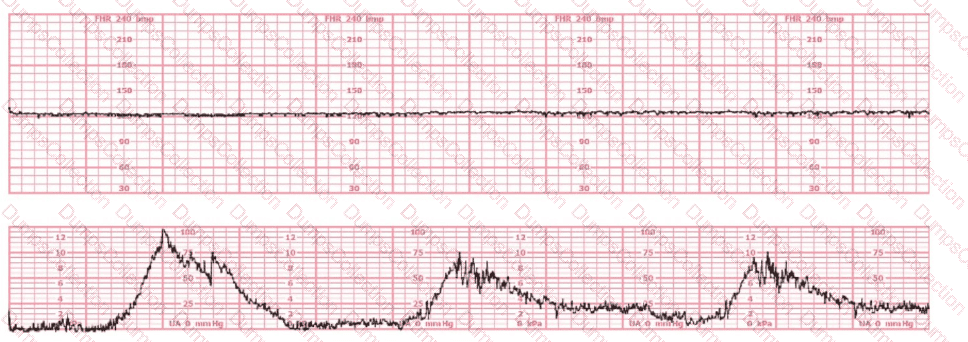

The tracing shown is from a woman at 28-weeks gestation in the post-anesthesia care unit (PACU) after an appendectomy. She is alert and awake. Based on this fetal heart rate pattern, the most appropriate intervention is: